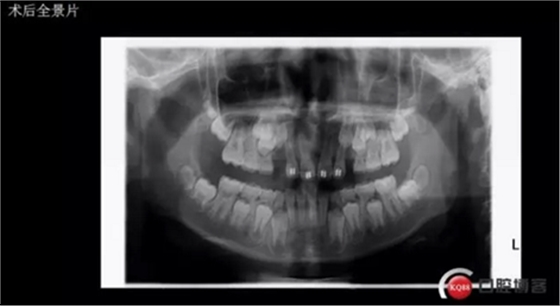

術(shù)后思考:患兒如今已經(jīng)十一歲多, 雖然已經(jīng)給尖牙騰出了位置,然而全景片顯示兩顆尖牙位置依然很深,是主動(dòng)出擊還是靜觀其變呢?歡迎大家共同探討!